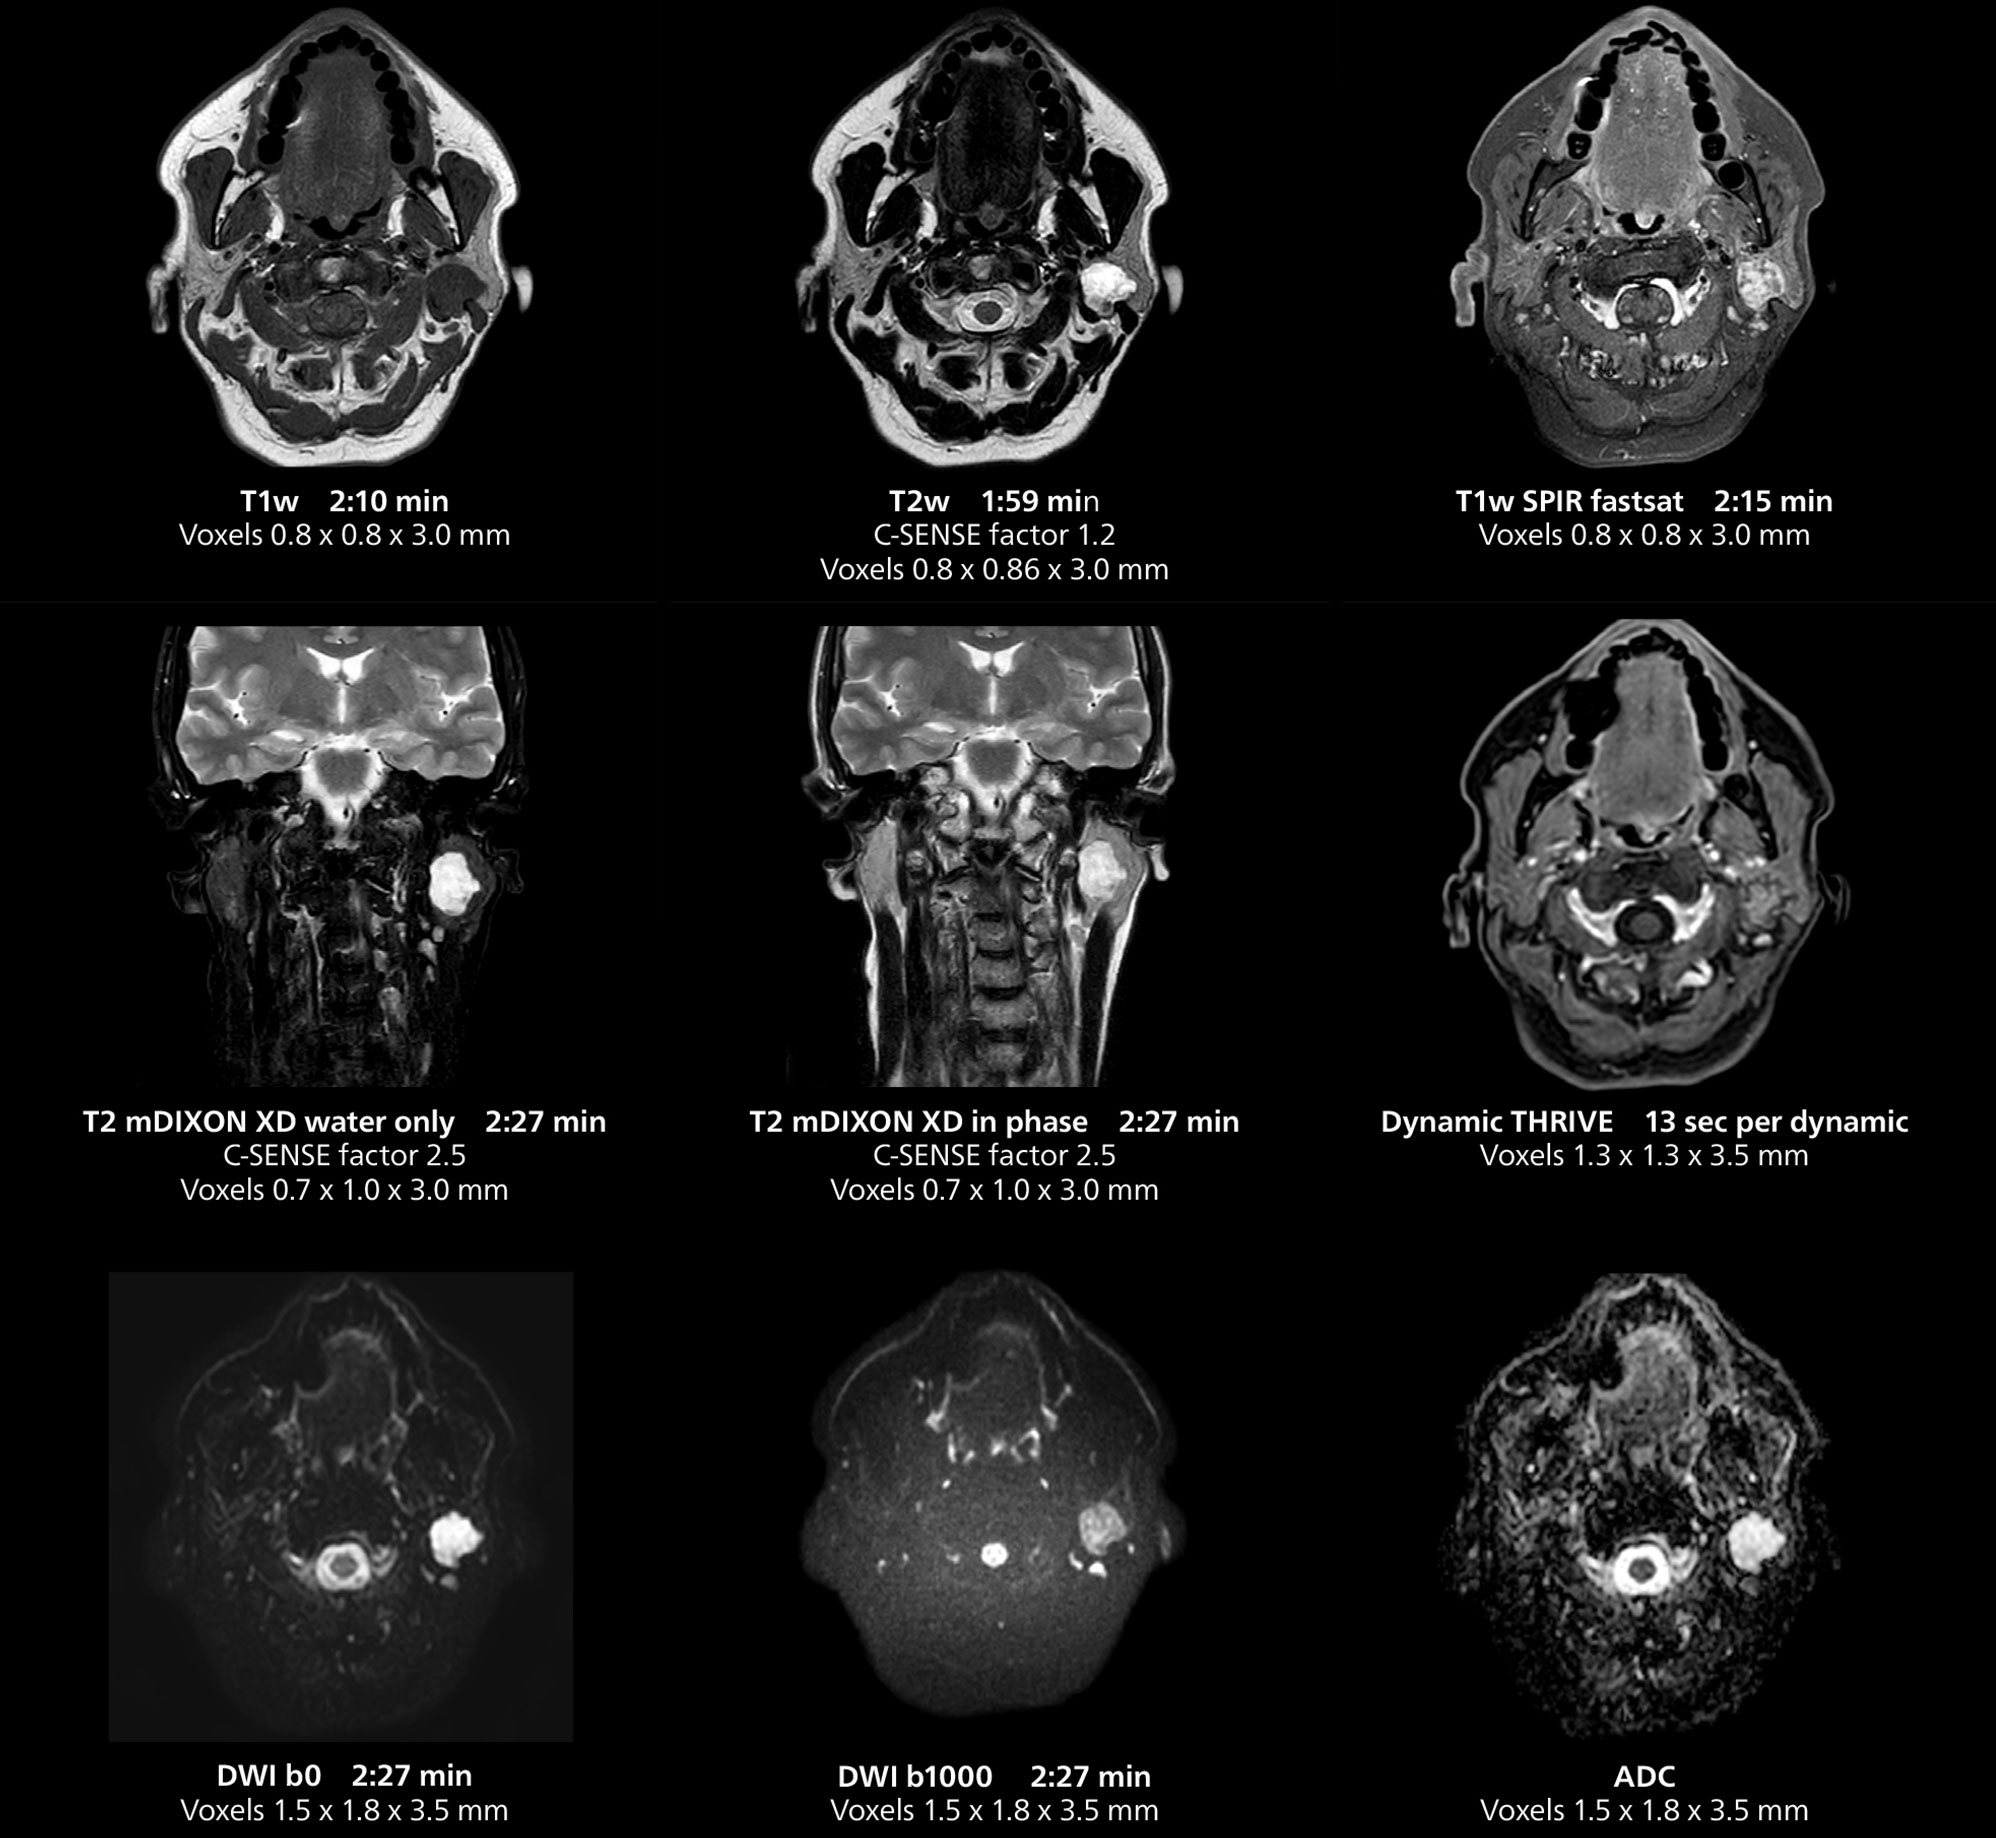

Le système MR 5300 doté de Compressed SENSE est jusqu’à 50 %** plus rapide pour de nombreux examens. Il permet de réaliser des examens de routine en moins de 5 minutes et des examens du corps entier en moins de 20 minutes. Saint-Augustin a su profiter de cette rapidité pour créer des protocoles très efficaces. La procédure d’AVC standard de l’hôpital ne dure qu’environ 8 minutes, et les examens ORL standard, la classification PIRADS de la prostate et les examens de l’endométriose ne durent tous qu’environ 10 minutes***.

“Les séquences 3D sont plus rapides”, affirme le Dr Gellée. “Avec Compressed SENSE, nous pouvons remplacer deux ou trois acquisitions 2D par une acquisition 3D de haute qualité. Des orientations supplémentaires de haute qualité peuvent être obtenues par post-traitement de l’ensemble des données 3D, ce qui permet d’économiser du temps d’acquisition.”

Cet exemple d’IRM illustre l’imagerie d’anomalies des glandes salivaires avec différentes séquences. Compressed SENSE permet d’accélérer l’acquisition tout en conservant une qualité élevée. Avec mDIXON XD, il est possible d’obtenir différents types de contraste à partir d’une seule séquence.